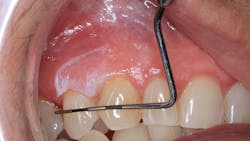

Patient: 2-year-old male

- Lump on right side of neck

- Ulcer-like lesions on buccal oral mucosa

- PCP diagnosed patient with hand, foot and mouth disease

A week later …

- Fire-engine red gingival tissue

- Manifestation of numerous perioral lesions

- Fever, loss of appetite, myalgia

- No lesions on hands or feet